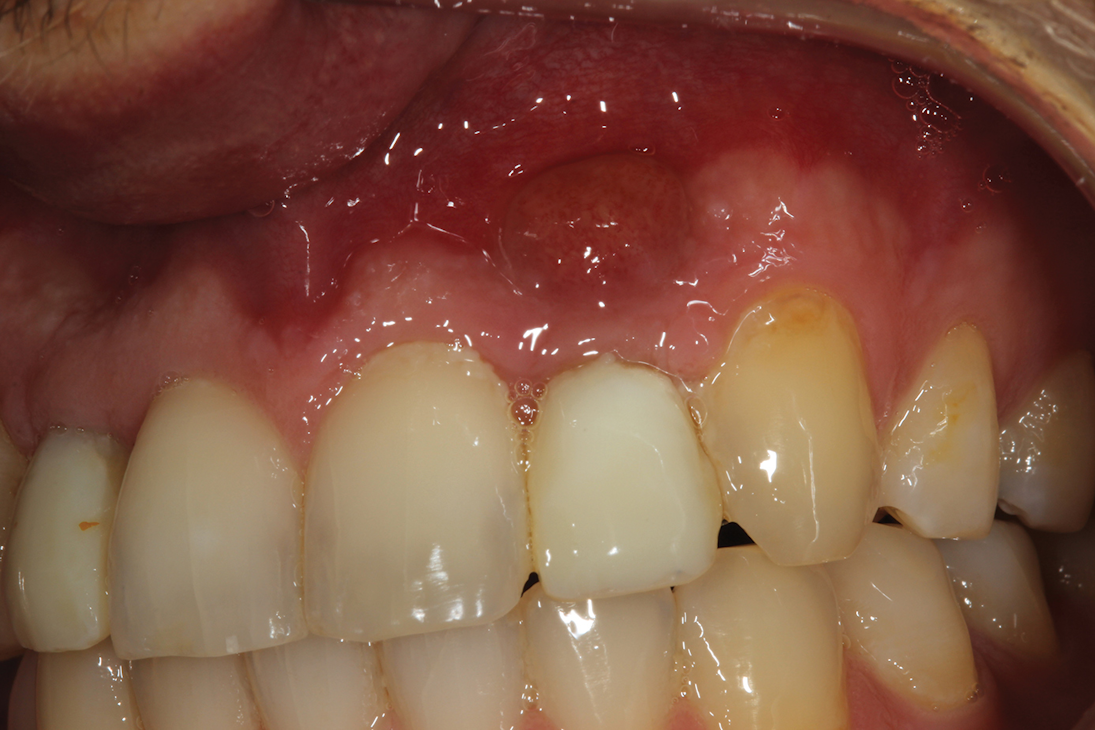

Ive been doing everything as prescribed by the d. Bone graft surgery is a beneficial treatment that restores your oral health after you have lost jaw bone due to tooth loss and gum disease. Gum grafting can also help build up bone in areas of the mouth to allow the placement of dental implants.

Caring for a dental bone graft is similar to the way you would care for many types of oral surgery sites. After the bone graft you may experience soreness that can be treated with ibuprofen and an ice pack. You may notice some swelling or bruising at the surgical site.

This is normal and not generally a cause for concern. Dental code 4 bone graft material. Dentistry Dental Issues.